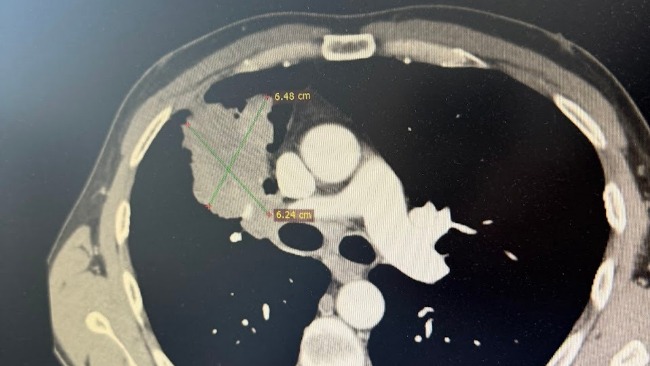

Rezonans głowy wykazał mnogie przerzuty do mózgu. Tomografia klatki piersiowej ujawniła guz prawego płuca z przerzutami do drugiego płuca oraz do węzłów chłonnych. Zmiany pojawiły się także w kościach biodrowych, a lekarze podejrzewają ogniska w wątrobie.